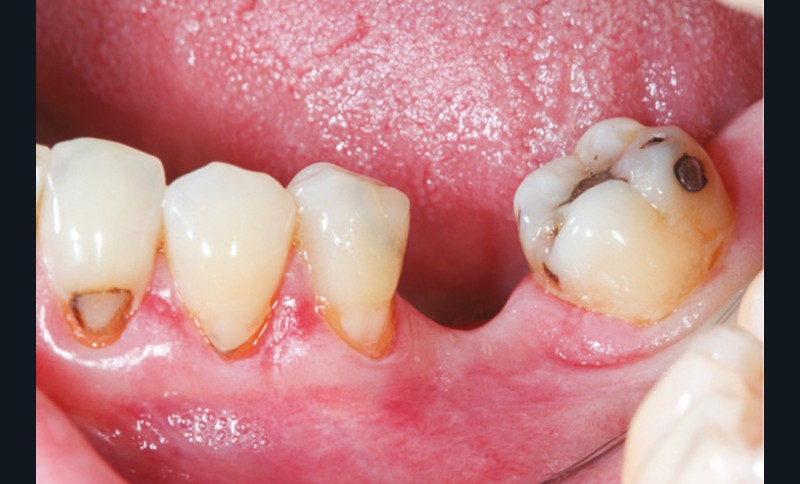

La perte d’une ou plusieurs dents entraîne la perte des points de contact, responsables de la stabilité et de la continuité de l’arcade. Par conséquent, une avulsion a pour première conséquence la migration ou la version d’une ou plusieurs dents distales (fig. 1 et 2). Cela est vrai en antérieur comme en postérieur.

Cette version, quand elle se produit, modifie les espaces interdentaires et complique l’hygiène proximale des patients. Des caries peuvent alors se développer en interproximal sans que cela soit forcément visible à l’examen visuel (fig. 3 et 4). Les radios de type bite-wing (rétro-coronaires) prennent alors tout leur sens (fig. 5 et 6).